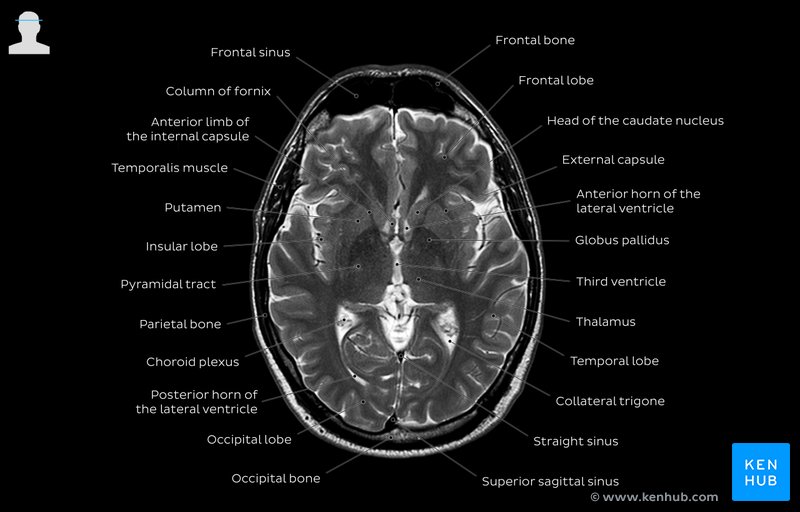

Description: ct brain labeled